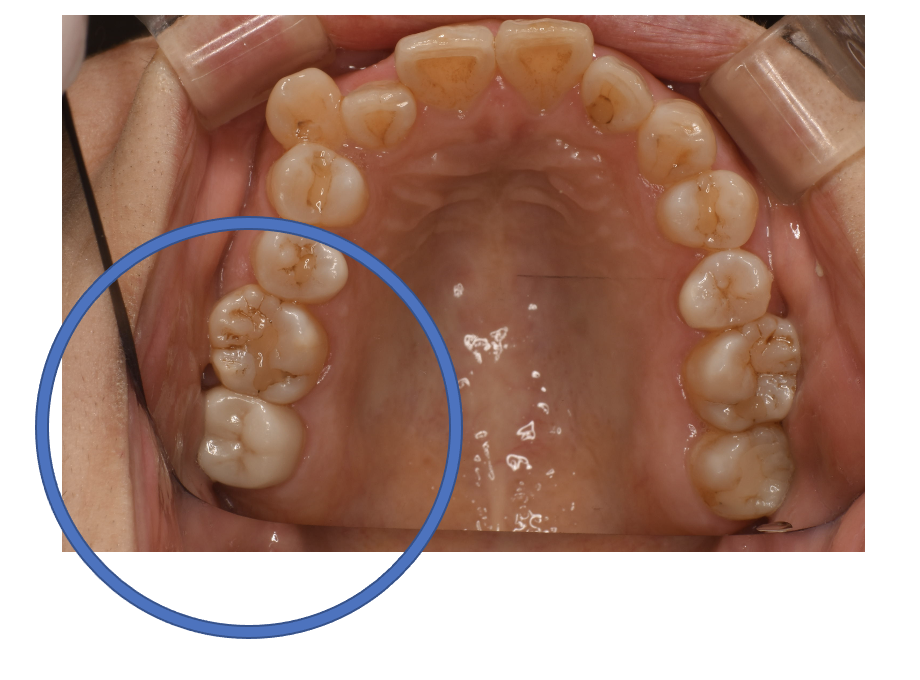

Before

| 備考 | 院長より 銀歯の内部に虫歯が進行してしまっていたケースです。中を開けて見てみると、外から想像するよりもはるかに虫歯が広がってしまっていました。幸運にも神経を保存できたので、生きた臓器としてまだ使うことが可能です。残存歯質がかなり薄く弱くなってしまったので、ジルコニアで被せて守ってあげています。しっかりとした治療ができたので、まだまだ長く使っていけるでしょう。 |